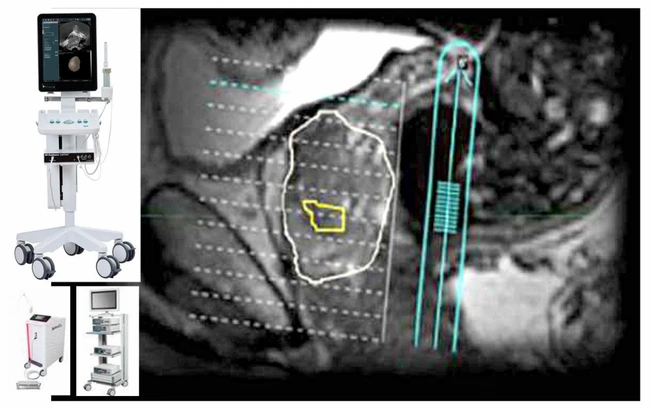

Puncţia biopsie prostatică de fuziune (fusion biopsy) reprezintă în prezent cea mai performantă metodă de diagnosticare a cancerului de prostată. Aceasta presupune fuzionarea imaginilor multiparametrice prin rezonanţă magnetică (mpMRI), care evidenţiază o zonă suspectă, cu imaginea ecografică obţinută în timp real la ecograful de ultimă generaţie bk3000, specializat pe Urologie. Suprapunerea se face prin intermediul unui software special, bkFusion.

Fuziunea realizată de ecograful bk3000 oferă o hartă tridimensională a prostatei şi a leziunilor prostatice suspecte şi ghidează acul de biopsie direct în zonele suspecte de cancer. Astfel, utilizarea puncţiei ghidate mpMRI se asociază cu o detectare crescută a cancerului de prostată semnificativ clinic, comparativ cu biopsiile obişnuite.